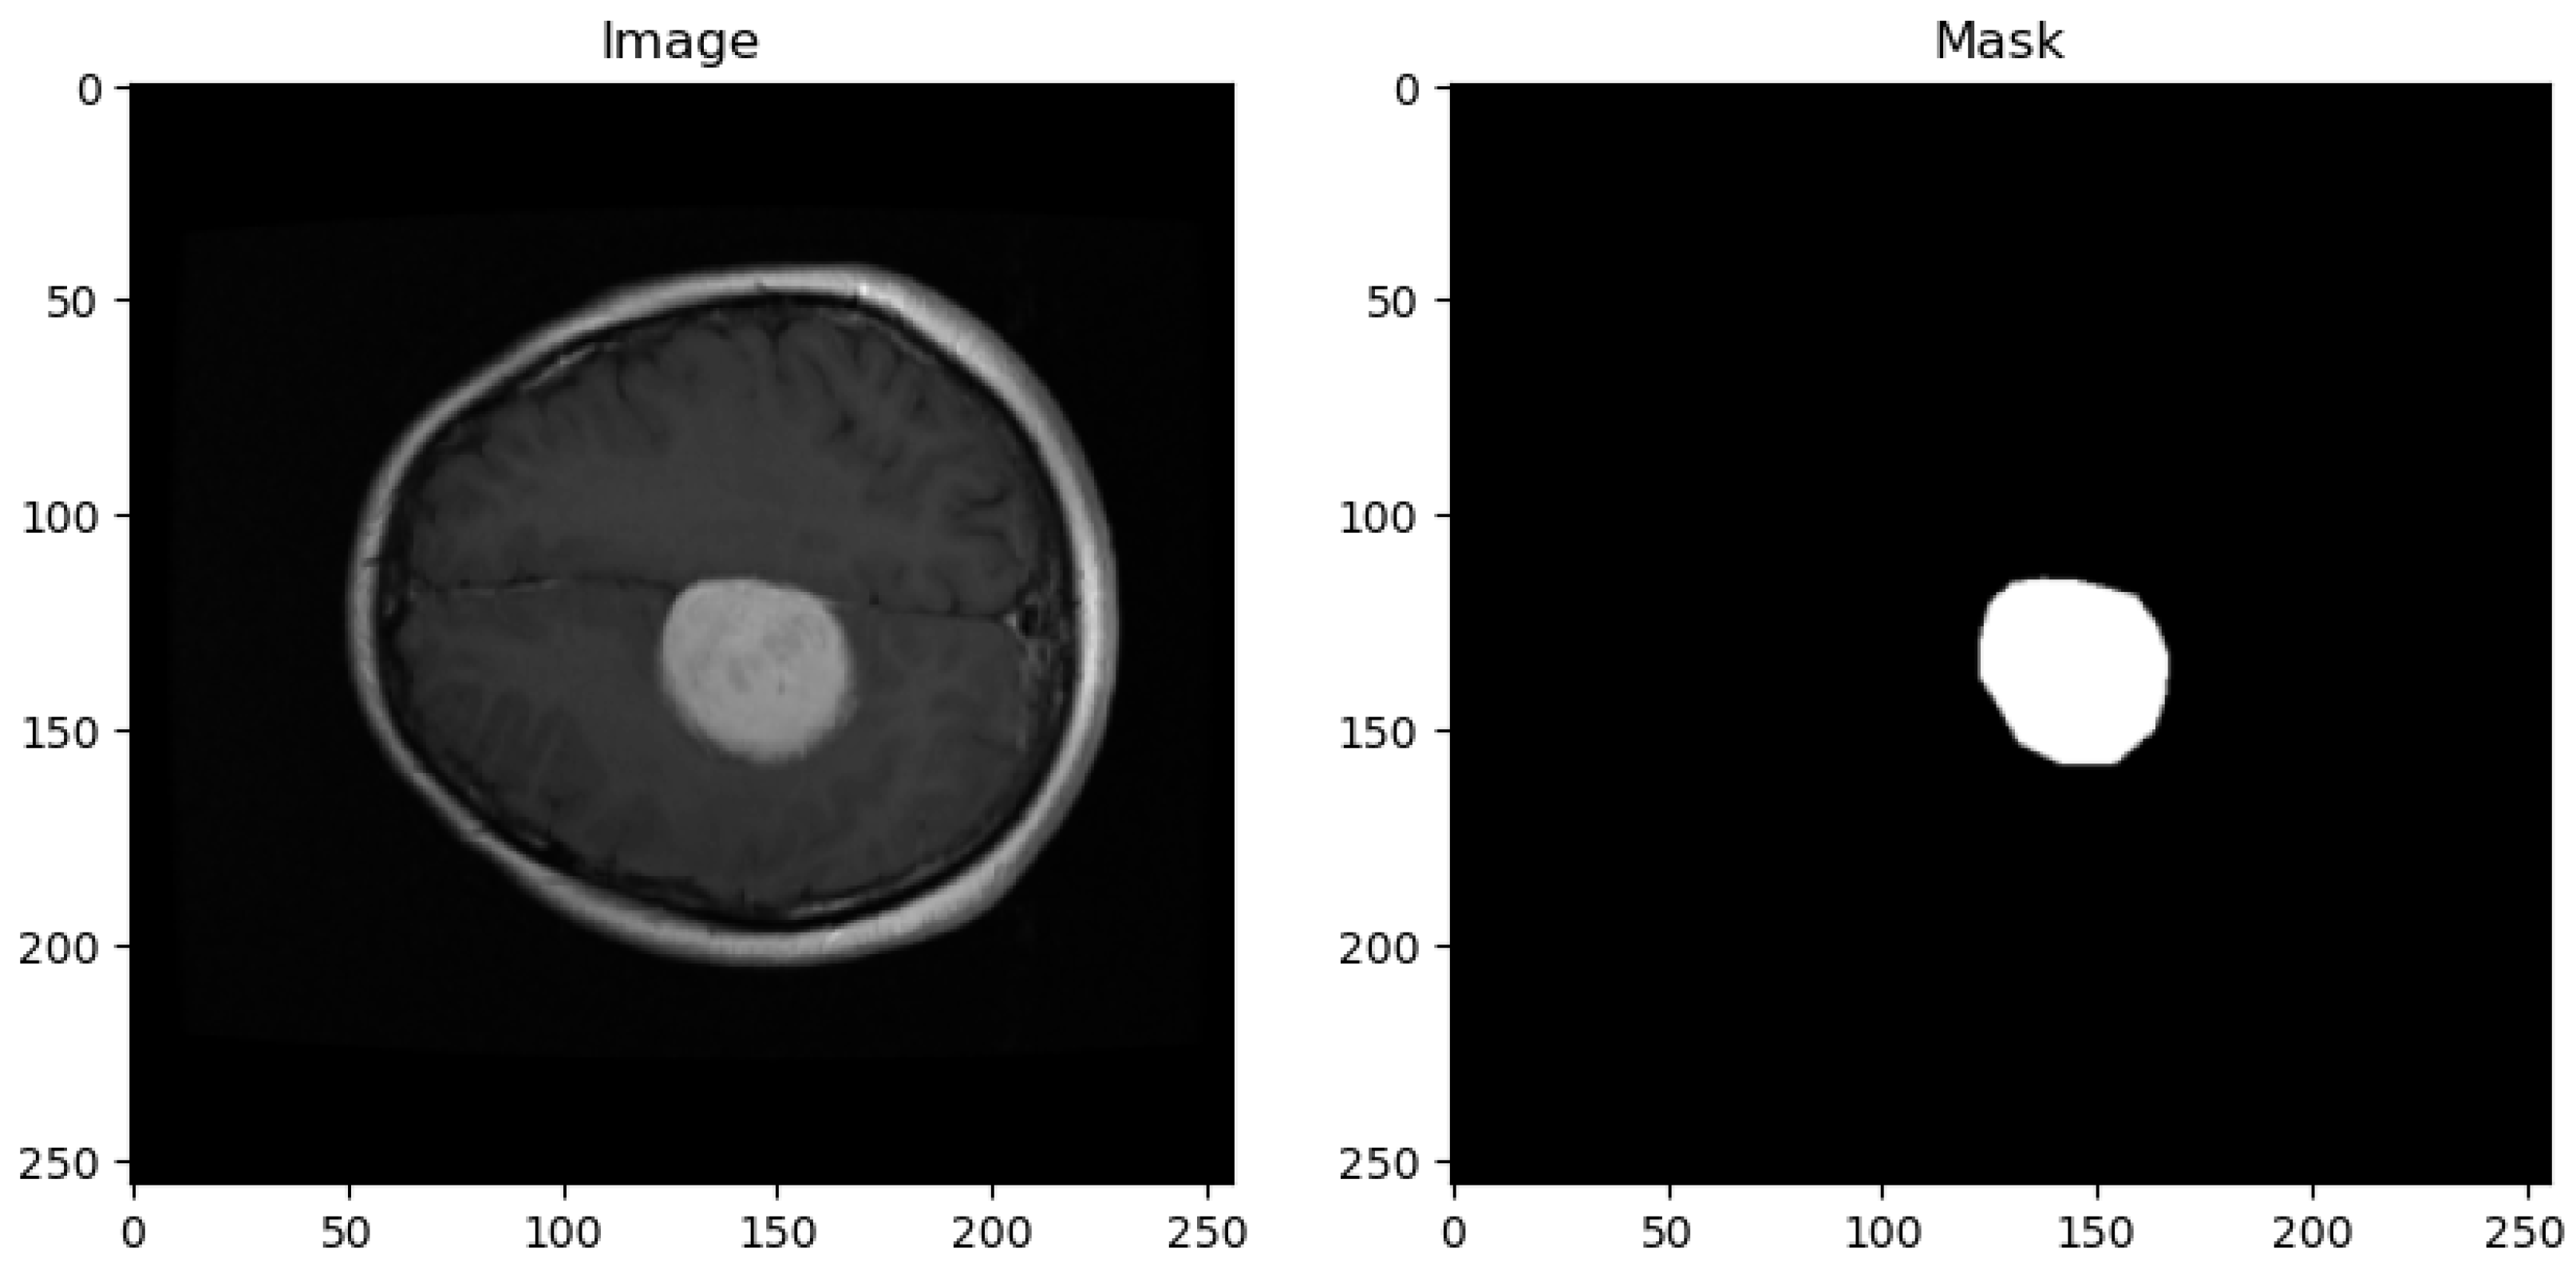

- Original Image: The pipeline receives the MRI scan as its initial input, showcasing a comprehensive cross-sectional view of the patient’s brain and potential pathological features.

- Ground Truth Mask: Next to the original image is the ‘Ground Truth Mask’, meticulously annotated by clinical experts to delineate the regions of clinical significance, such as lesions or tumors.

- Predicted Mask: The segmentation branch of our pipeline then predicts a mask, endeavoring to replicate the expert annotations by encapsulating the region of interest highlighted in the MRI scan.

- Annotation Details: Each MRI image entry in the dataset is accompanied by essential information, including the class name (tumor type), patient ID, image data, tumor borders (defined by x and y coordinates outlining various points on the tumor’s boundary), and a binary tumor mask representing the segmented tumor area.